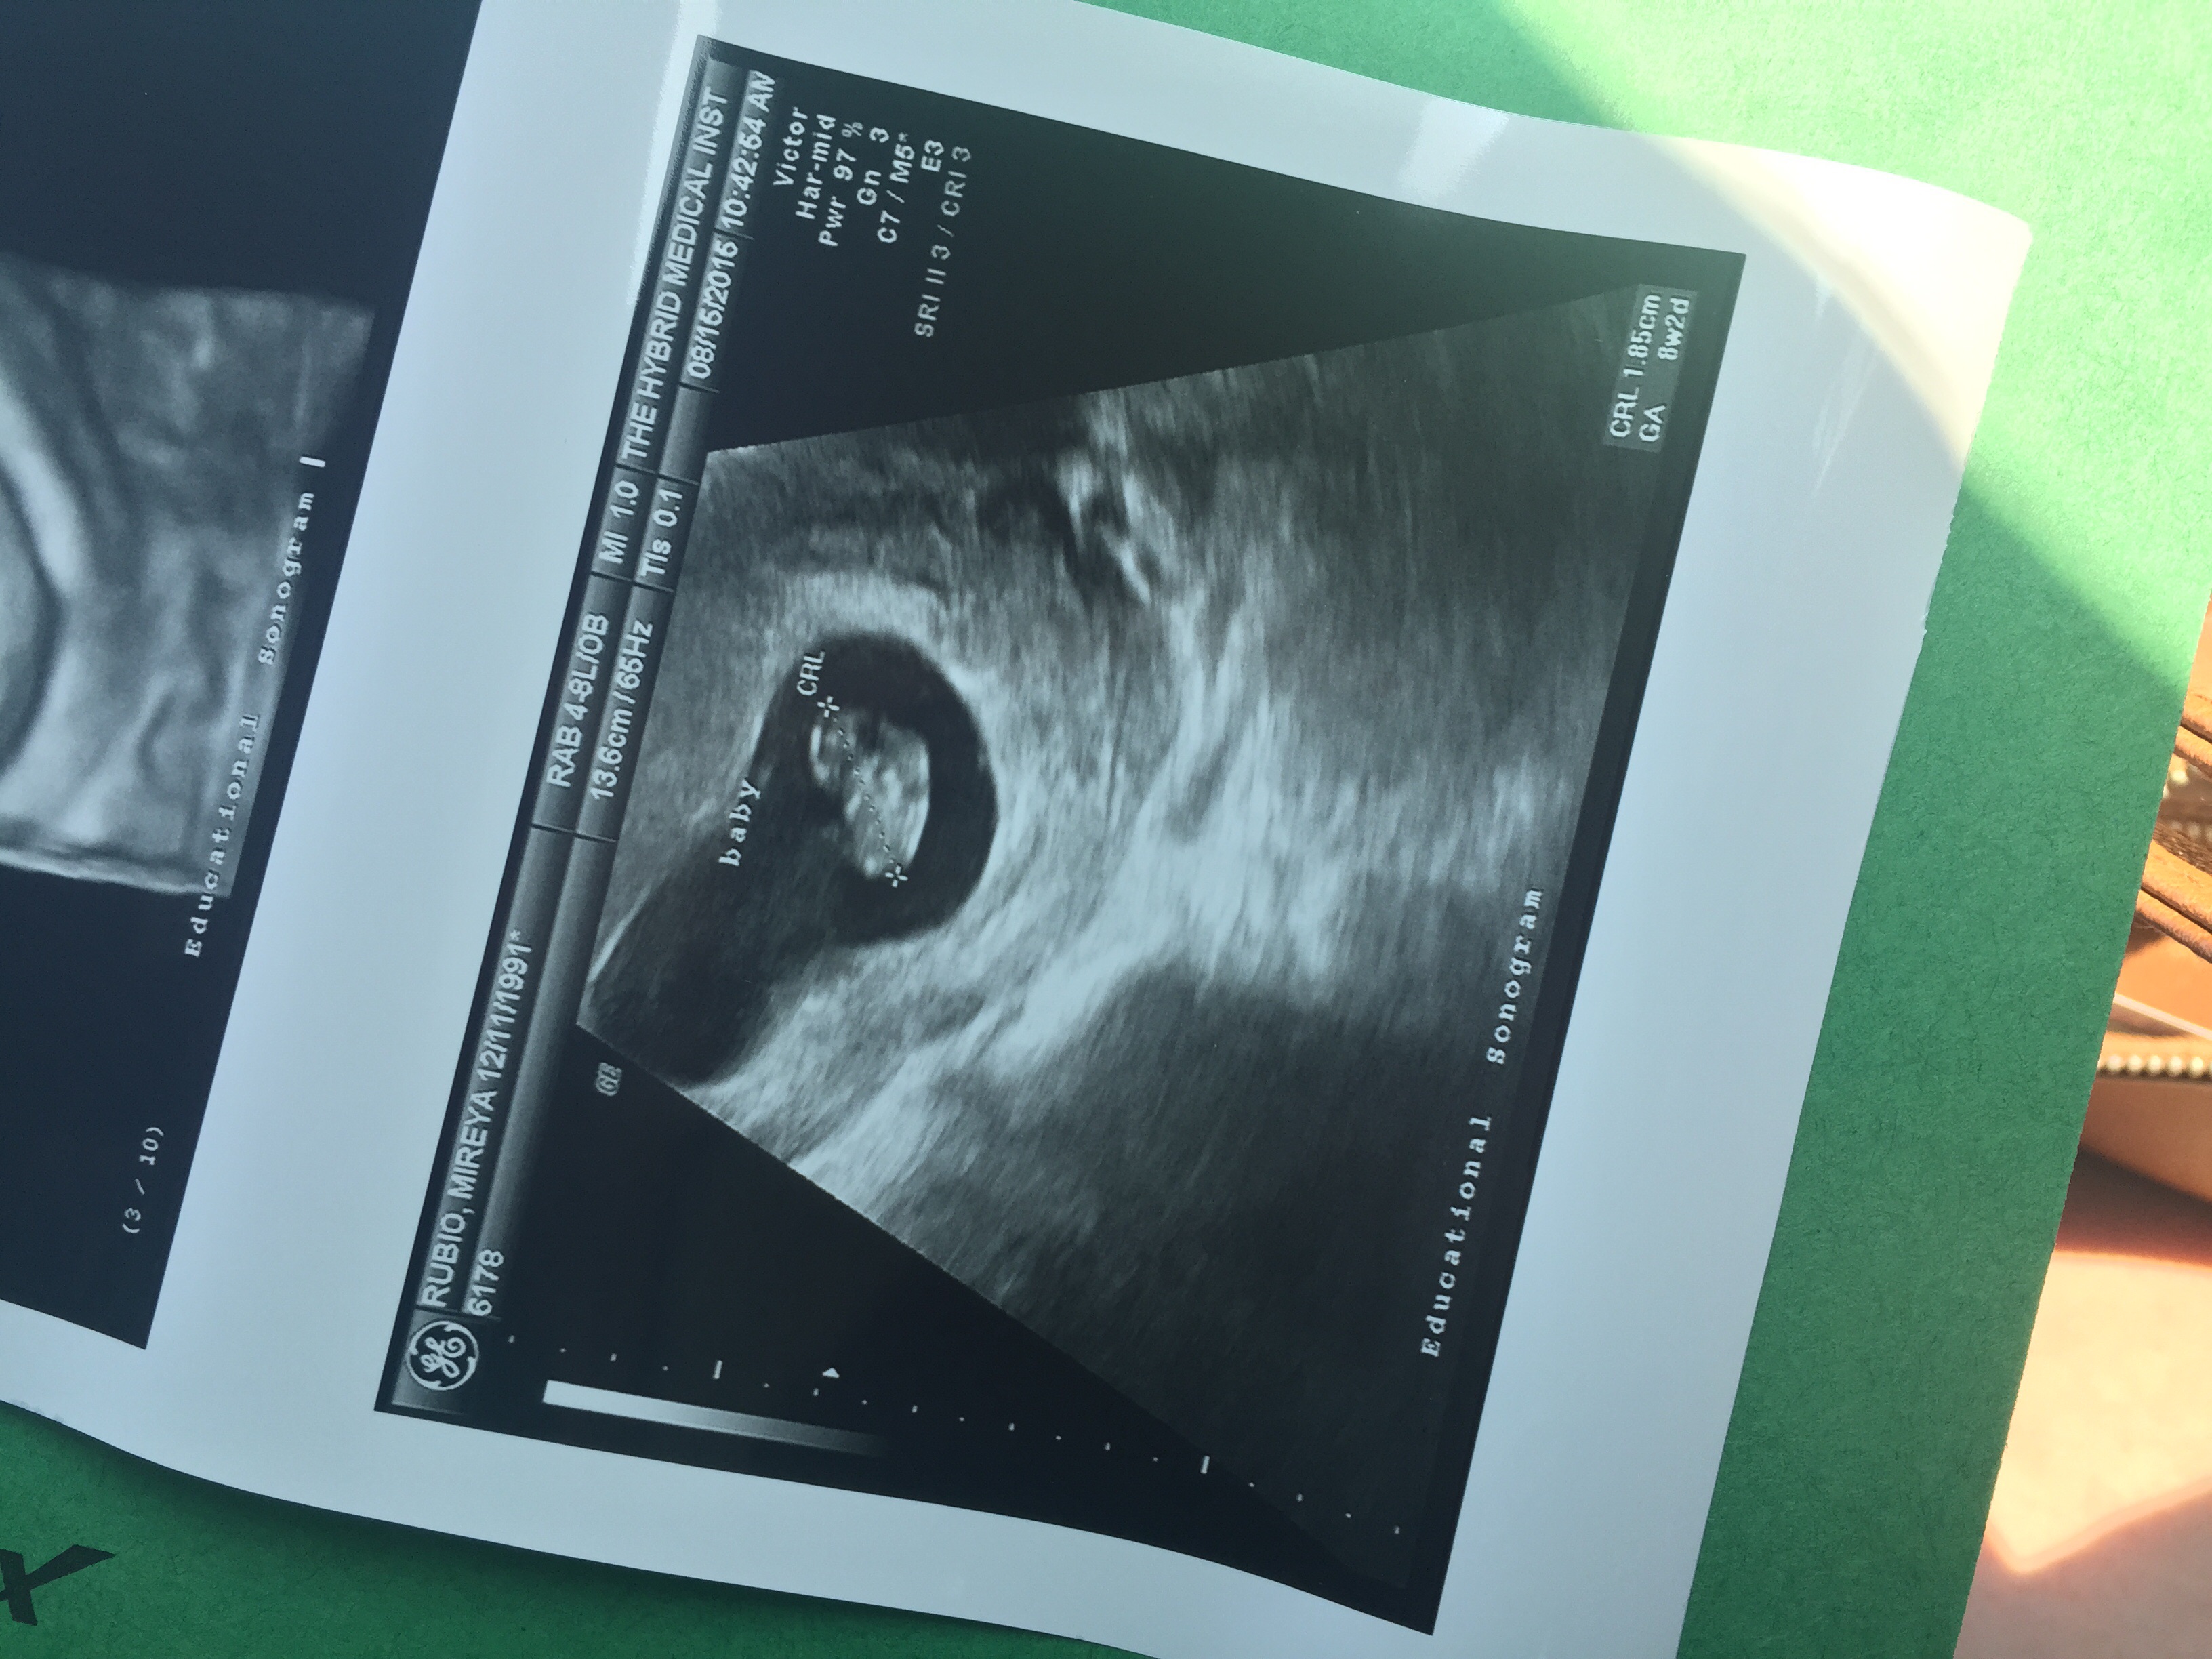

I can't really tell in your US! I can see the placenta in mine so I have a better idea of how it translates to the Ramzi method.

Re: Help with Ramzi Theory! 8wks abdominal u/s

Edited to add: there's a 50/50 chance of having either a boy or a girl. Ramzi is no more accurate than flipping a coin.